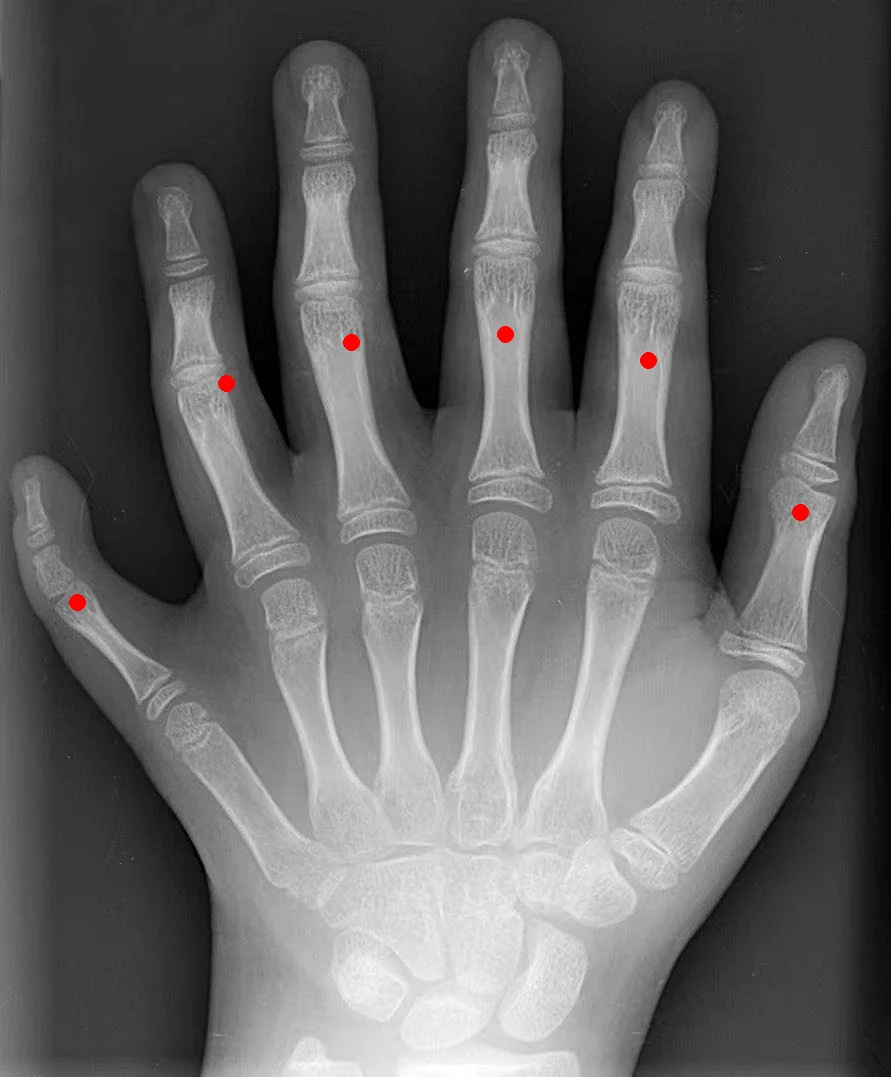

模型能在图片中精准定位目标物体。几个有意思的例子:

数手指:给一张手部 X 光片,让模型用坐标标出所有手指的位置。模型准确识别并标注了 6 个手指(包括左右两侧拇指和中间 4 个手指)